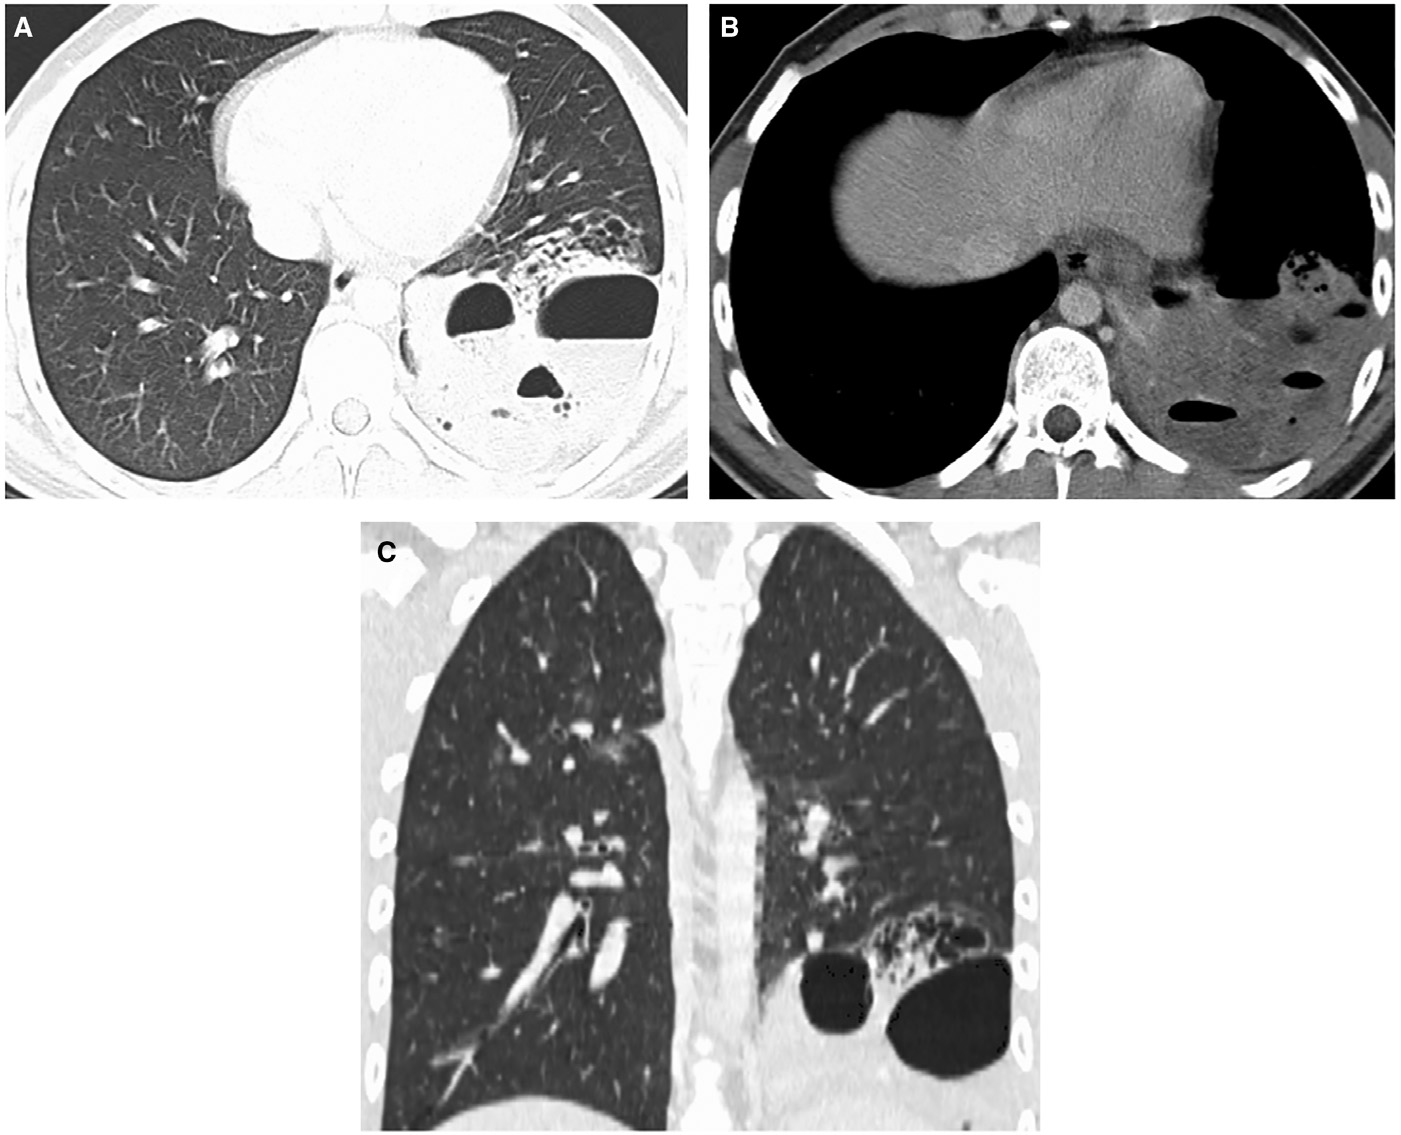

實(shí)驗(yàn)室檢查顯示白細(xì)胞計(jì)數(shù)13.6×109/L↑(中性粒細(xì)胞79%;淋巴細(xì)胞12%),C反應(yīng)蛋白96 mg/L↑。胸部X線檢查顯示左肺下葉實(shí)變伴氣液平面,考慮與空洞性肺炎相關(guān)(圖1)。增強(qiáng)CT顯示左肺下葉病變,有空氣支氣管征和含氣液平面的空洞及囊狀氣腔。(圖2A–2 C)。人類免疫缺陷病毒抗體檢測、抗中性粒細(xì)胞胞漿抗體、尿肺炎球菌和軍團(tuán)菌抗原檢測均為陰性,且多組血培養(yǎng)結(jié)果顯示無菌?;颊呦惹拔催M(jìn)行IgG及亞類缺陷檢測。

圖2 軸向(A)、(B)和冠狀(C)CT圖像顯示左肺下葉病變伴空洞、氣液平面、相鄰囊性空腔和周圍實(shí)變。